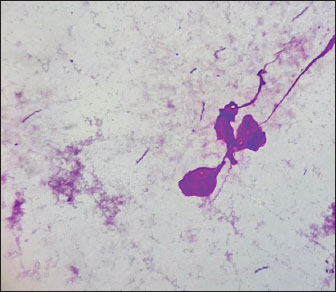

Furthermore, we analyzed imprint smears derived from biopsy samples collected during endoscopic procedures of the gastric mucosa in cats to indicate the presence of Helicobacter species. As a result of the microscopic examination of the imprint smears, spiral bacteria were observed in three cases (30%) with low colonization density, and in 4 cases (40%) with moderate colonization density (Fig. 2).

Fig. 2. Imprint smear of the gastric mucosa in a cat (moderate colonization density by helicobacter). Staining according to Romanowsky’s method. Original magnification ×900.